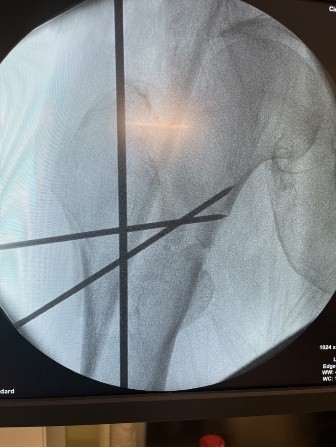

Hip fractures in the elderly are quite frequent and result in a high morbimortality rate [3,4]. The functional impairment leads to considerable social as well as economic implications due to the inability of the patients to perform their daily activities [5,6]. The morbidity of unilateral hip fractures ranges from 40 to 50% in women and from 13 to 22% in men [7], which is quite a high incidence. Contrary to this, simultaneous bilateral PFFs are not that common; therefore, there is a lack of data in the literature regarding the management of these injuries. According to Grisoni et al., over the period of 10 years, only eight cases were reported, with a frequency of 0.3% of the total number of hip fractures [8]. Furthermore, Verma et al. over the period of 3 years presented only four cases of simultaneous bilateral PFF with a rate of 0.24% [9]. Because of the low incidence of these types of injuries, there is no established, reliable treatment protocol yet, making these patients unique and demanding in the treatment process. Rodriguez-Zamorano has reviewed and analyzed the corresponding literature related to simultaneous bilateral PFF, and they have identified three patient profiles: “(i) Young patients involved in a traffic accident with multiple associated injuries, for which the definitive surgical intervention was sometimes delayed, having an impact on the overall survival. (ii) Patients aged 65–75 years old with fractures in the context of high-energy accidents. (iii) Patients over 80 years who sustain fragility fractures after casual falls from their height”[1]. An interesting fact that must be emphasized here is that our case does not fit into any of the above-mentioned patient profiles because the patient is above 85 years old and has sustained a high-energy trauma. In this course of events, this case would make an independent “fourth” profile of patients with simultaneous bilateral PFF. There are different approaches regarding the surgical treatment of simultaneous bilateral extracapsular hip fractures. We decided on proceeding with intramedullary fixation bilaterally since it offers better results compared to extramedullary fixation – shorter intraoperative time, smaller surgical wound, lower infection rate, less blood loss, and earlier weight bearing. There is an ongoing debate about whether to ream the intramedullary canal. While reaming allows usage of a thicker implant – thus biomechanically more stable fixation, on the other hand, it increases intraoperative time and the risk of fat embolism syndrome, especially in patients with bilateral proximal fractures. Furthermore, adult respiratory distress syndrome is considered significantly higher in bilateral fractures [10]. In our case, we decided not to use reaming in either of the fractures. Closed reduction and percutaneous K-wires were used for the fixation of the right intertrochanteric fracture (Fig. 6), whereas open reduction and percutaneous K-wires were used for the fixation of the left subtrochanteric fractures since closed reduction was unsatisfying (Fig. 7).

Figure 6: Right hip. Closed reduction and percutaneous K-wires.